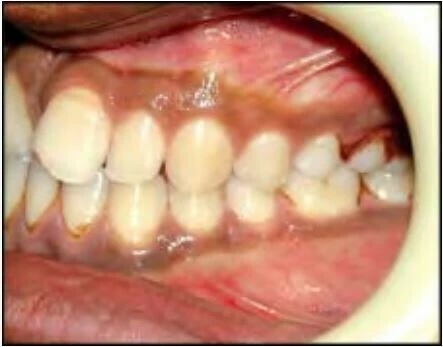

Khớp cắn nằm về phía trước so với bình thường

Với loại này, khi các răng gặp nhau tại khớp cắn trung tâm thì cung răng hàm dưới nằm về phía trước hơn.

Khớp cắn nằm về phía sau so với bình thường

Ở đây, khi các răng gặp nhau tại khớp cắn trung tâm thì cung răng hàm dưới nằm về phía sau hơn.